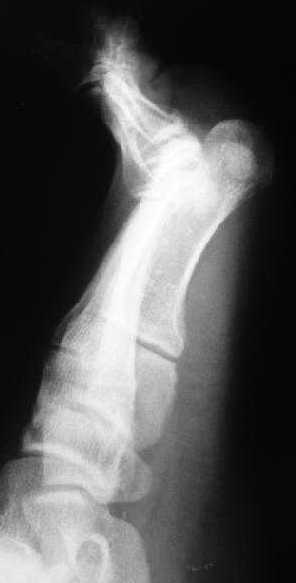

1 передний отдел стопы делается в косой, а не боковой проекции - на боковой все плюсневые кости накладываются друг на друга, и ничего не видно - это же аксиоматично! Я, например, на прямых проекциях не вижу совсем признаков перелома первой и четвертой плюсневой, и сомневаюсь в переломе третьей, боковые же совершенно неинформативны.

Как же суть проблемы видна? Человек говорит о переломе первой (то есть речь идет о переломо-вывихе?), второй, третьей и четвертой плюсневых костей, а я вижу только перелом второй. мне кажется, что проблема в таком случае будет чуть-чуть другая. Кстати, сколько переломов насчитали на этих снимках Вы?

Однозначно-переломы 1,2,3,4 плюсневых костей.

Имеем - без малого двухмесячные переломовывихи перeднего отдела стопы , больной в отделении 20 дней, доктор думает, что ему делать:

Не знаю, что за проблема, но я на своем мониторе переломы отлично вижу.

Та же проблема - по крайней мере на снимке в аппарате (фас) отчетливо видно перелом ее головки.